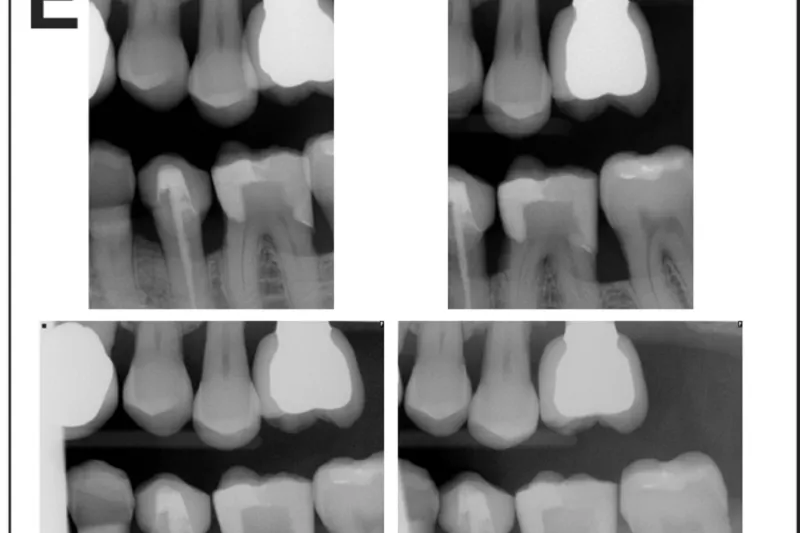

Formålet med undersøgelsen er at sammenligne den information, man får med to forskellige bitewingoptagelser, horisontale (HBW) og vertikale (VBW).

I røntgenjournaler fra Tufts University School of Dental Medicine (TUSDM) blev der søgt efter patienter, som havde knoglesvind omkring kindtænder og havde fået foretaget både HBW og VBW. I alt blev 320 journaler gennemgået efter seks kriterier: synlighed af marginal knogle fra hjørnetandens distalflade til den bageste tands distalflade, synlighed af horisontalt eller vertikalt knoglesvind, densitet af marginal knogle, synlighed af approksimale kontaktområder, synlighed af hele den anatomiske krone samt synlighed af furkaturer.

Der var signifikant flere VBW end HBW (P < 0,0001), der viste tab af det marginale knogleniveau (52,81 % vs. 3,75 %), typen af knoglesvind (vertikalt eller horisontalt) (50,94 % vs. 3,75 %), knogledensitet (28,75 % vs. 0,63 %), kontaktområder (20,63 % vs. 14,38 %) og furkaturer (43,44 % vs. 1,25 %). Der var flere HBW end VBW, der viste hele den anatomiske krone. Der var ingen signifikant forskel på antallet af optagelser pr. sæt HBW og VBW.